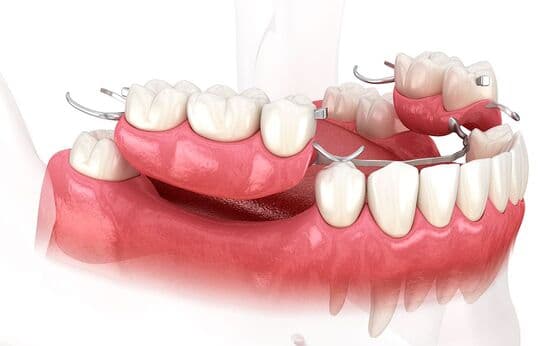

入れ歯治療

入れ歯は、歯を失った部分を補う取り外し可能な人工の歯です。部分入れ歯と総入れ歯があり、手軽に咀嚼機能を回復できます。外科手術が不要ですが、噛む力が天然歯より劣り、装着時の違和感が生じることもあります。

入れ歯治療について

入れ歯の噛む力は天然歯やインプラントに比べると、10%~40%と言われており、入れ歯が大きくなるほど咀嚼能力は低下します。しかし、入れ歯治療はインプラントのような異物を体内に入れたり、ブリッジのように歯を削ったりしないので、歯を失った時の治療では生体への侵襲は一番低い治療になります。